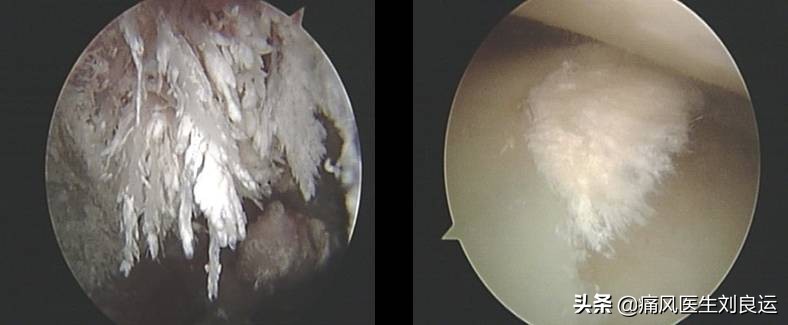

针刀镜下关节内散在尿酸盐结晶

针刀镜通过钝剥关节内滑膜、软骨表面及充分灌洗关节腔,清除关节滑液及滑膜、软骨表面的致炎因子和沉积物,减轻其引起的机体免疫应答反应,从而遏制疾病进展。同时,通过解除关节内外的组织黏连、剥削增生的滑膜和尿酸盐结晶,改善关节活动度,恢复关节功能。针刀镜能明显缓解难治性痛风石关节炎患者关节疼痛和改善关节功能,结合药物治疗,能减轻全身炎症程度和降低血尿酸水平。

在镜下对附着在软骨、滑膜及软组织中的痛风石进行剥离、刮除、清理

针刀镜下痛风石沉积关节的尿酸盐结晶